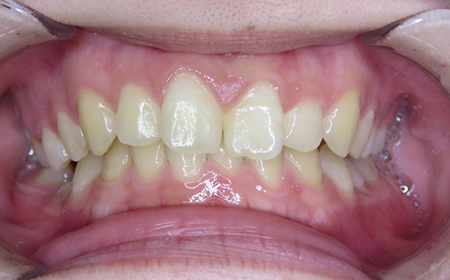

CASE02

Before

After

| 施術名 |

インビザラインGoを用いた矯正治療(叢生) |

| 治療期間 |

4ヶ月 |

| 治療費 |

437,800円(税込) |

| リスク |

マウスピース装置により疼痛・咬合時痛を生じる事があります。割れたり壊れたりする事があります。 |

歯科医師からのコメント

人と話す機会の多いご職業で、以前より「前歯のがたつき」が気になるとのことでご相談にいらっしゃいました。仕事中も目立たず、仕事に支障がでなくてよかったと仰っており、とても満足しておられました。